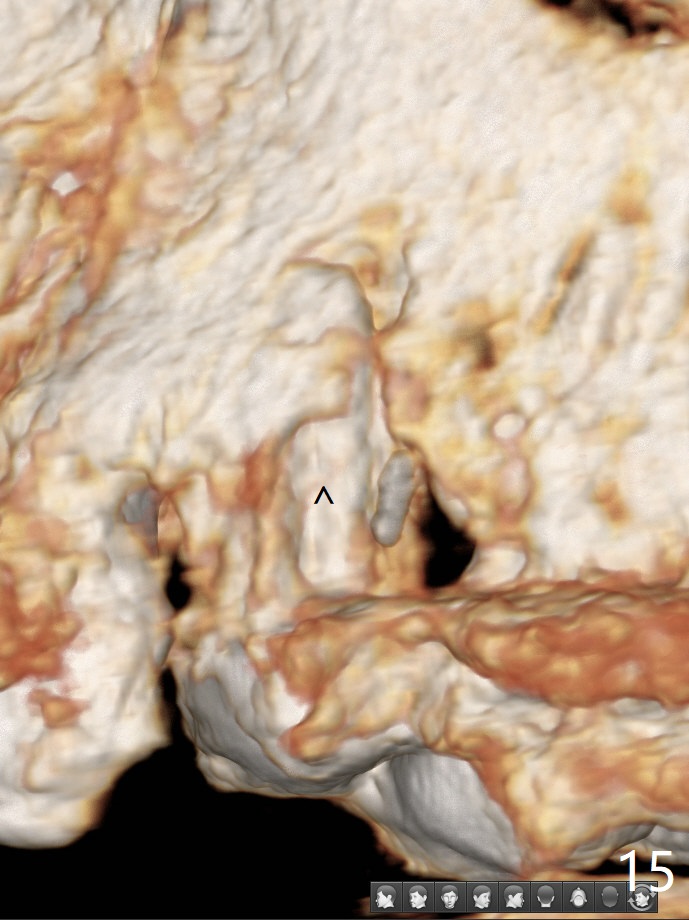

In spite of severe apical infection (Fig1,2 *), a thin narrow strip of the buccal plate (arrowheads, corresponding to the keratinized gingiva) is present when the tooth #11 is extracted. The thin bone keeps the bulging alveolus, i.e., reservoir for bone graft (Vanilla/Osteogen Fig.4 *) after placement of a 3.8x16 mm implant (Fig.3,4). A 4.5x1 mm temporary abutment, placed and trimmed for an immediate provisional, seems to be short in cuff. When an implant is placed deep to prevent periimplantitis, the cuff should be longer, i.e., 3 mm. X-ray should be taken for the depth confirmation after temporary abutment placement. Eight days postop, the mesial gingiva erythema has subsided (Fig.5 < (P: provisional)), while the apical swelling is no longer tender and most likely due to packed bone graft (*). Panoramic X-ray taken 2 weeks postop shows the clearance from the nasal cavity or the maxillary sinus (Fig.6). While the hard tissue around the implant seems to be healthy 5 months postop (Fig.7), the soft tissue is not (Fig.8). The temporary abutment is changed to a cemented one (4.5x5(2) mm) for impression (Fig.8). Since the neighboring crowns are PFM (Fig.6), the new crown will be made of the same material for shade match. Indeed PFM helps shade match in this case as well (Fig.9,10). Switching abutments (from temporary to cemented) makes it difficult to seat the crown. Post cementation X-ray leaves record for future contact loosening. The buccal gingiva remains erythematous associated with open margin (Fig.11 >) 1 year 4 months post cementation. There is no obvious bone loss 1 year 4 months post cementation (Fig.12). It appears that the crown and abutment need to be changed. Although the gingival margin remains erythematous, the gingival hemorrhage is basically lacking due to better oral hygiene during Shelter at Home (1 year 9 months post cementation, Fig.13). Change in abutment and crown will be conducted post coronavirus pandemic. In fact the abutment is incompletely seated (Fig.14 <). In addition, the tooth #12 is symptomatic with PARL associated with the buccal root (*). CBCT indicates possible buccal root fracture (Fig.15,16 ^) and loss of the buccal plate (Fig.16 <).